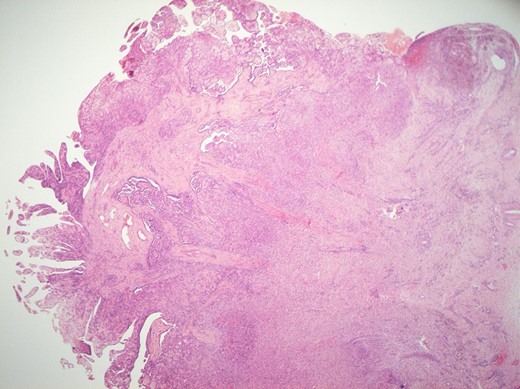

Histological features of the specimen were that of a fibrous cyst wall covered by cuboidal cells with bland nuclei (Fig. 1). Within the cystic space, there were branching, papillary structures with a fibrovascular core, lined with a single layer of bland cuboidal cells (Fig. 2). The stroma was oedematous and hyalinised. No sub-epithelial invasion was seen. There was no unequivocal cytologic atypia or atypical mitosis.

H&E staining of the specimen demonstrating branching, papillary structures with a fibrovascular core lined with a single layer of bland cuboidal cells.